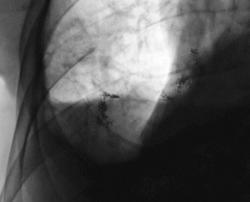

Правосторонний экссудативный плеврит с "затеканием" экссудата в главную междолевую щель. Плевра в междолевых щелях утолщена.